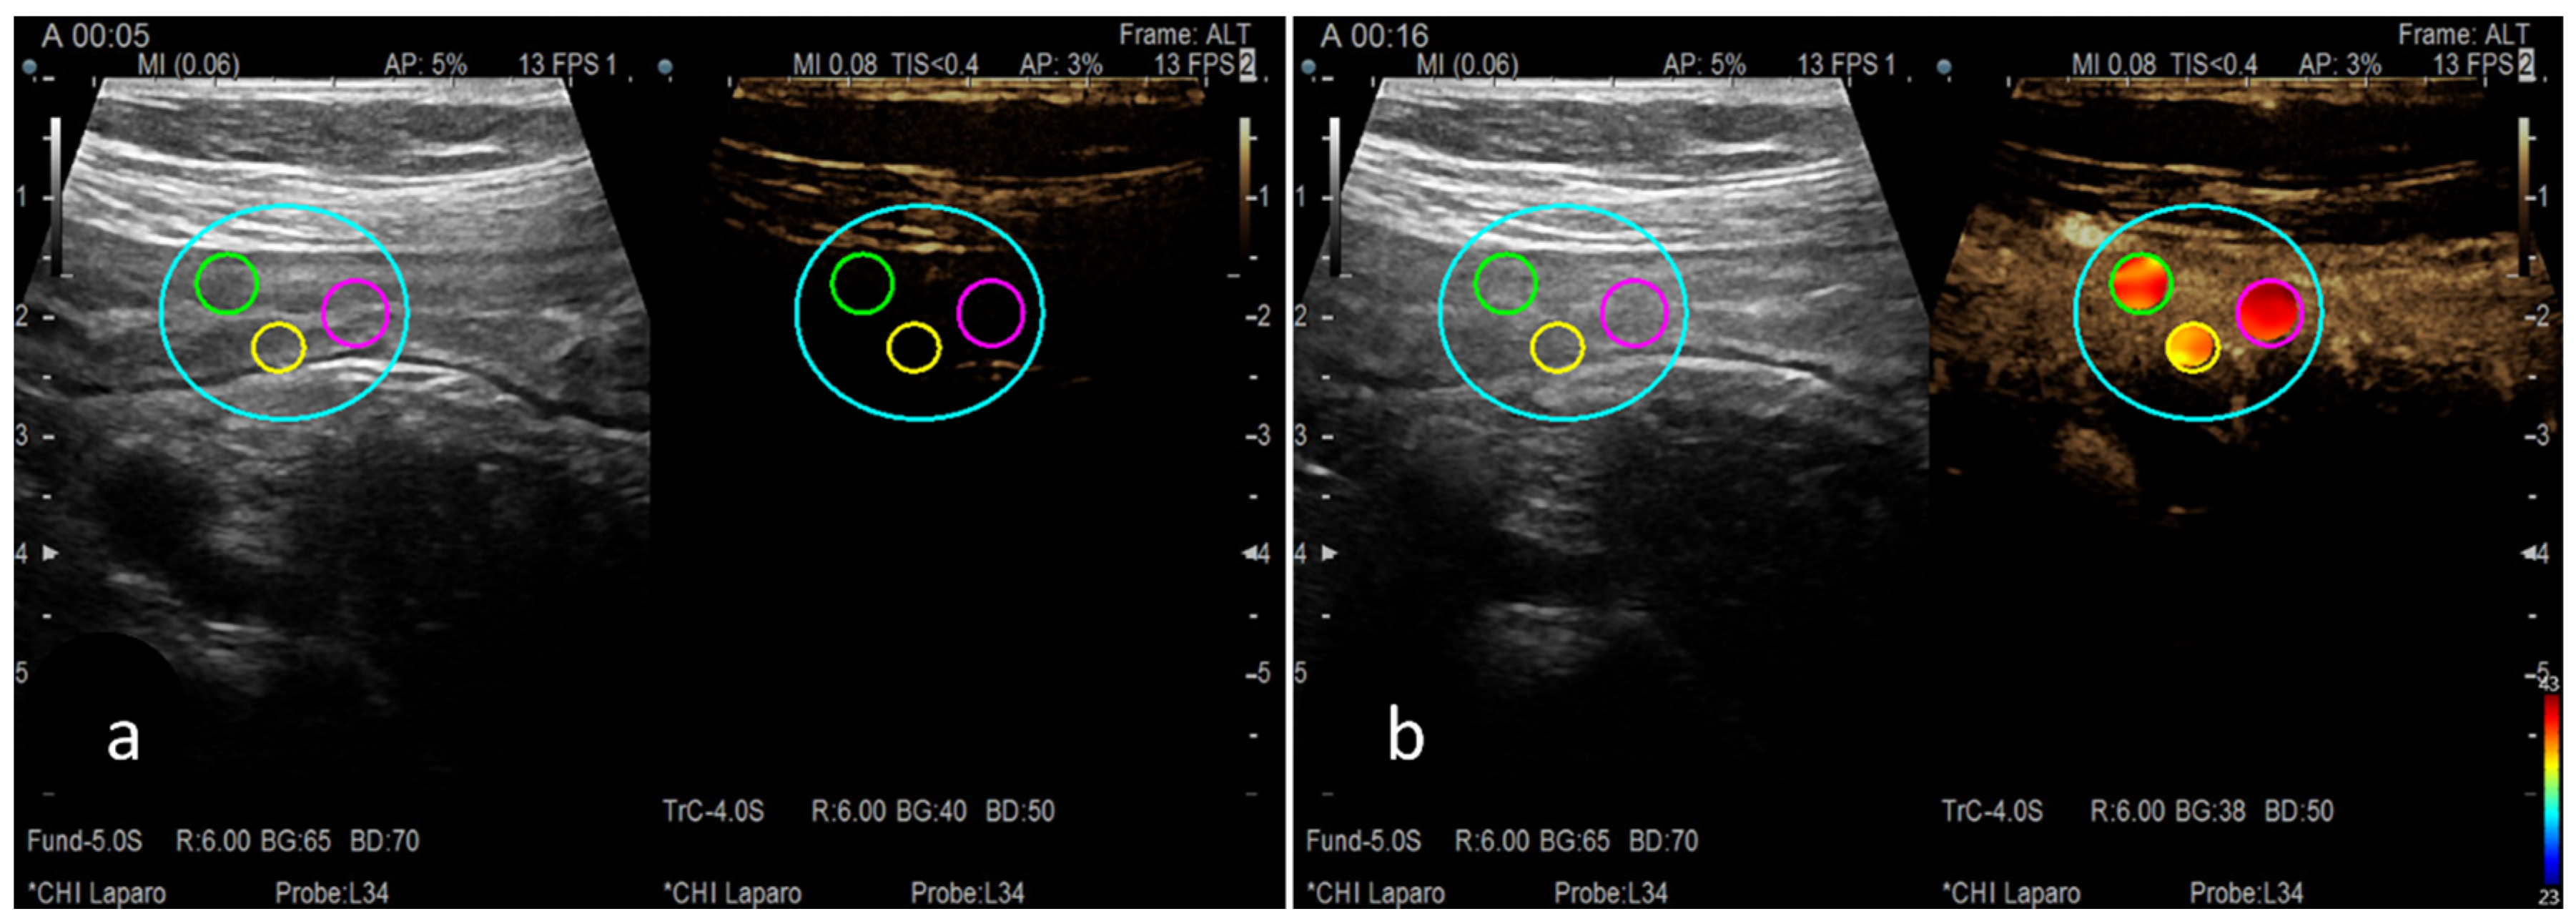

- Peak Enhancement (PE)—Figure 3b;